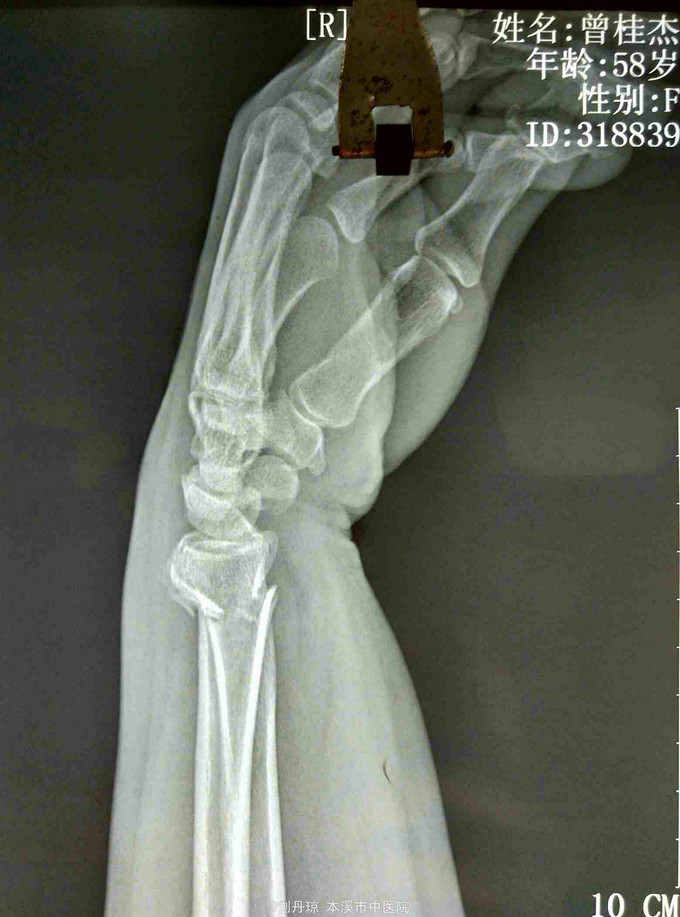

主诉:左腕刺痛,活动受限3小时。 病史: 患者3小时前不慎摔伤腕,伤后左腕刺痛,活动受限。遂来我院门诊求治。

诊断: 左colles骨折 治疗:手法整复,夹板固定,中药外用,接骨续筋中药口服。

随访|年。摔倒时腕关节极度背伸,使前臂旋前的扭力向前运动,导致此型骨折。colles 骨折占前臂骨折的75%,多见于中老年女性。colles骨折是最常见的骨折。典型表现为餐叉状畸形。主要包括然后远端向背侧移位和倾斜,桡偏,桡骨短缩,骨折常涉及桡腕关节和下尺桡关节。尺骨茎突骨折也是常见的合并损伤。